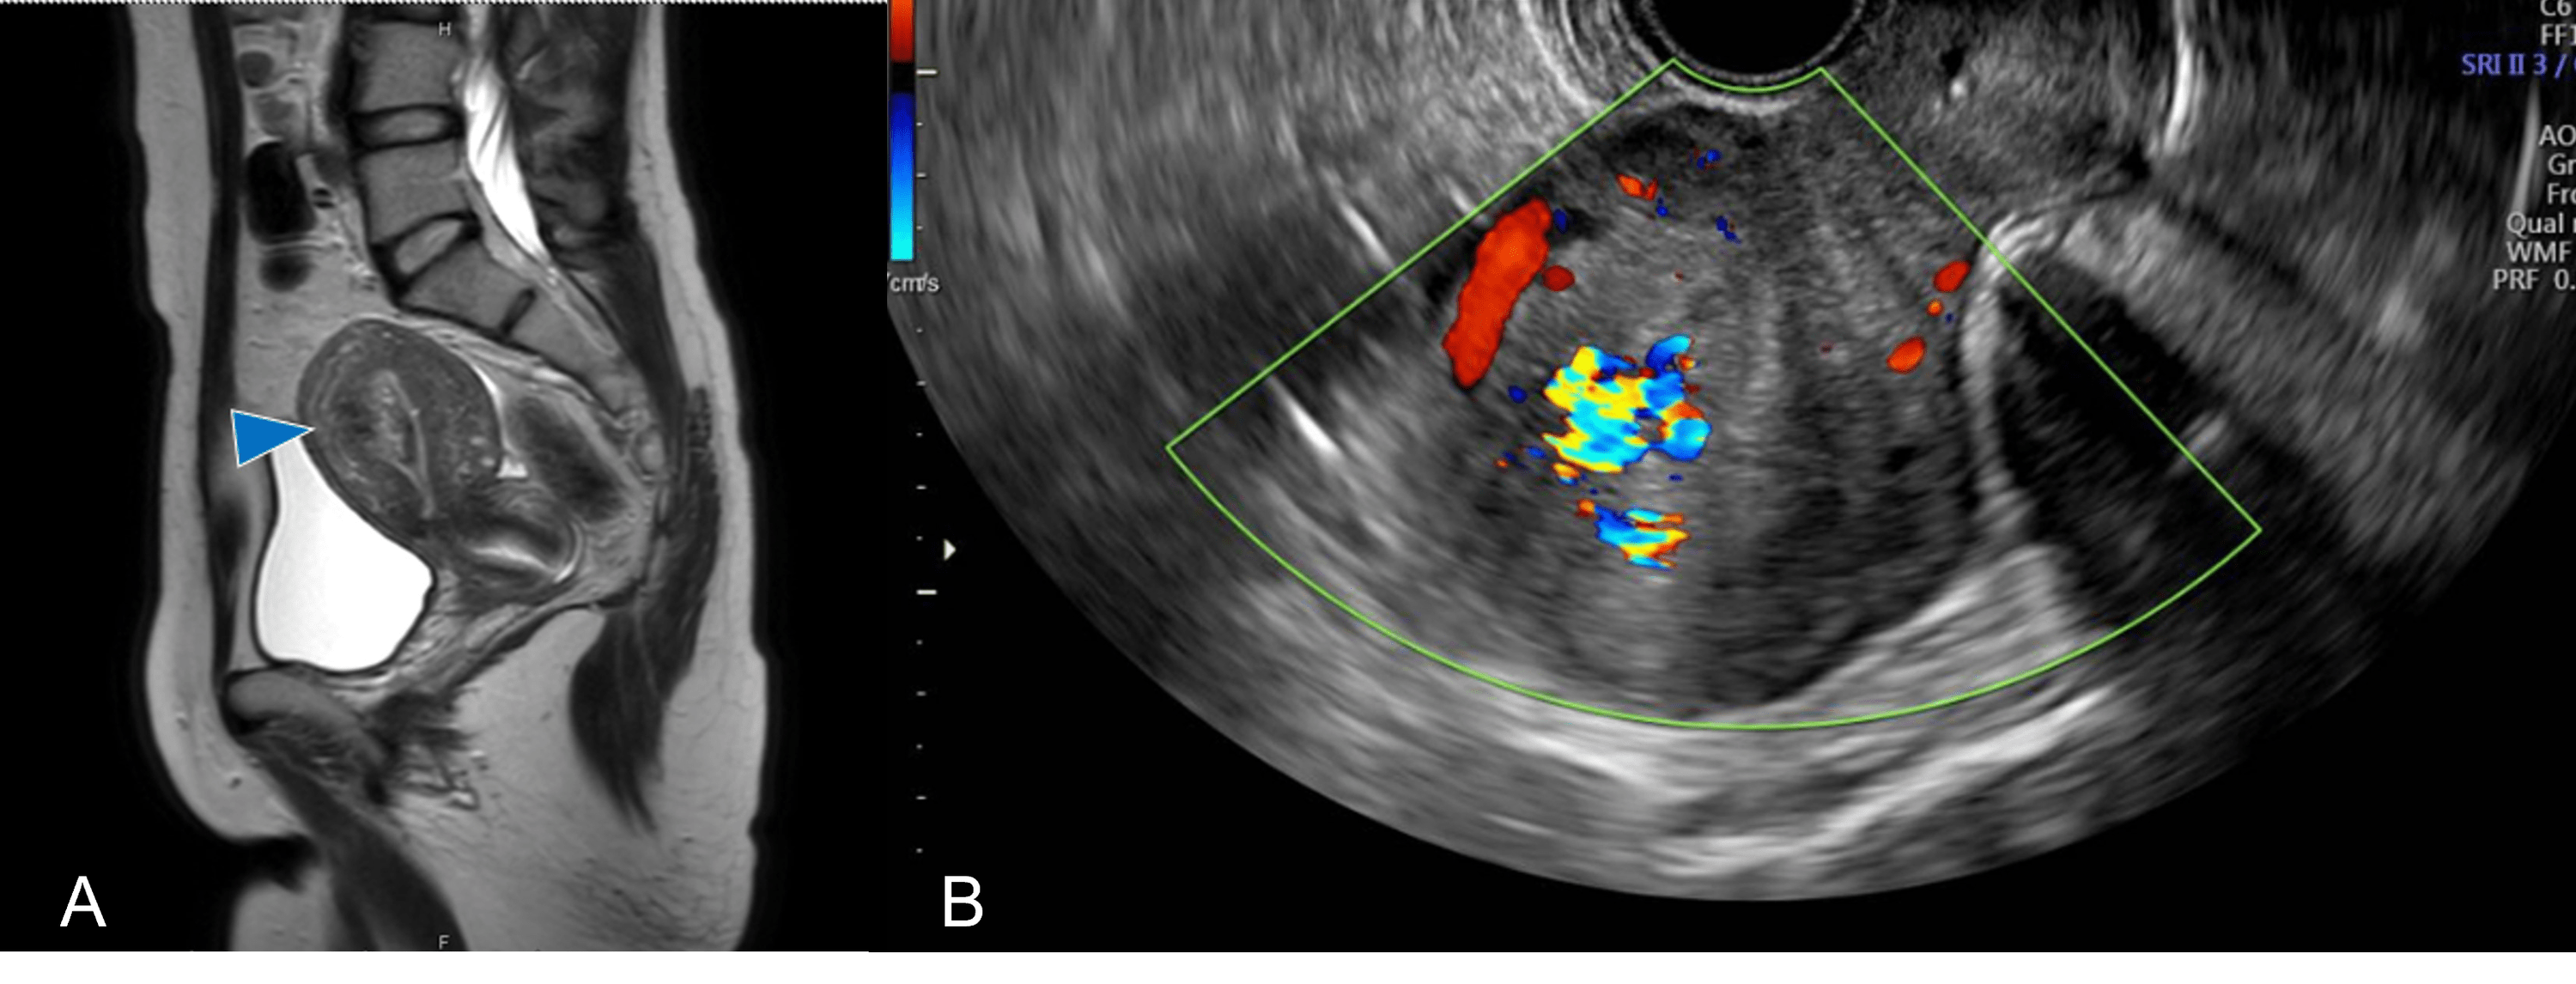

Ultrasound showing evidence of retained products of conception Retained Products Of Conception On Ct the term retained products of conception (rpoc) refers to placental and/or fetal tissue that remains in the uterus. retained products of conception (pocs) can occur after spontaneous or induced abortion and after delivery. They represent one of the. retained products of conception (rpoc) are a common and treatable complication after delivery or. retained products of conception. Retained Products Of Conception On Ct.